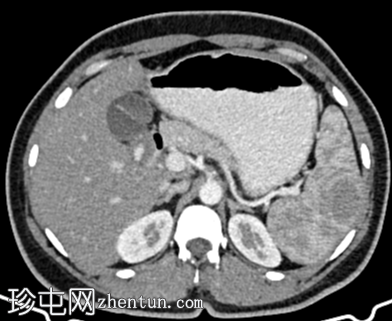

CT

轴位

平扫

轴位增强扫描

动脉期

门静脉期

脾脏内可见一圆形低密度病灶,动脉期呈周边环状强化,延迟期呈轻微向心性充盈

未见钙化、动静脉畸形或动脉瘤

脾脏硬化性血管瘤样结节性变是一种良

性病

变,常在中年女性中偶然发现。

影像

学特征为:病灶周围呈放射状强化,中心呈放射状强化,周围环状强化,中心充盈轻微。增强扫描后可见中央星状瘢痕。